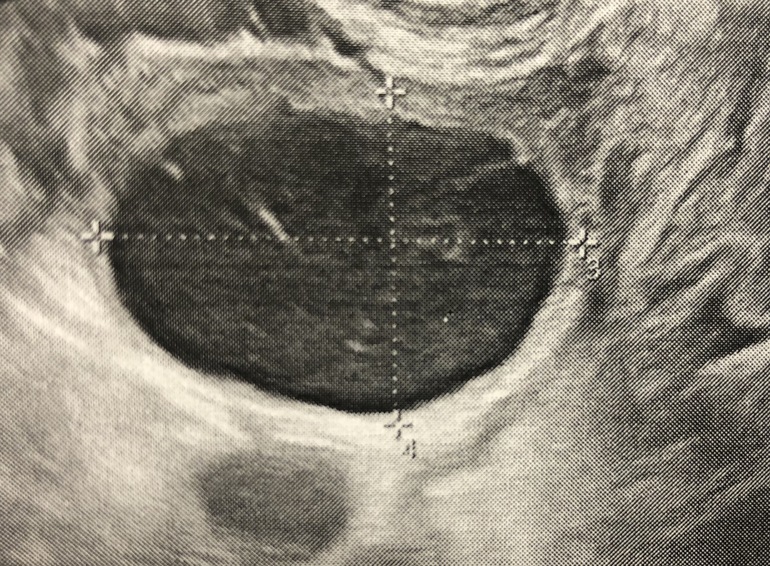

Доброе утро.На фолликулометрии нашли кисту жт 32*25 с васкуляризацией Написала:киста в os вероятнее всего «желтого тела» Так же сказала есть кровоток вокруг.Может ли это озночать неполноценную овуляцию?или при кистах жт всегда яйцеклетка выходит?Когда овуляция происходит в этом яичнике,всегда образуется киста!но овулирует он всего раза 2 в год.Узи у меня почти каждый месяц,по этому заметила.может все таки фолликулярная?

Киста ЖТ или фолликулярная - если есть кровоток периферический, то это ЖТ. Да и гипоэхогенное содержимое тоже для ЖТ более характерно.

Хм, ну если узист сомневается, то не знаю, но по идее вокруг фолликула не должно быть кровотока, да и стенка у этой кисты толстенькая такая. А содержимое у фолликула обычно просто чёрное, анэхогенное.

написано так:жидкостное образование с васкуляризацией в стенке ,с гипоэхогенным содержимым 32*25 с кровотоком вокруг.